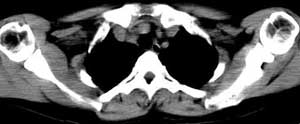

女 48岁 无意中发现左侧颈部肿块

甲状腺左侧叶下部结节状低密影,边界较清晰,考虑甲状腺肿瘤[腺瘤可能性大,恶性待排]

甲状腺左叶低密度病灶,边界尚清楚,邻近气管、血管、肌肉无明显侵润;考虑良性病灶,以甲状腺腺瘤可能大。

左侧甲状腺下极可见类圆形结节样低密度病灶,边缘清晰,未见明显周围组织受侵,颈部未见明确淋巴结肿大;右侧甲状腺形态密度未见异常。

诊断意见:左侧甲状腺结节样病灶,多考虑甲状腺腺瘤。建议ect检查。

双侧甲状腺弥漫性密度减低,左侧可见低密度结节边界清晰,周围软组织未见异常,考虑双侧结节性甲状腺肿